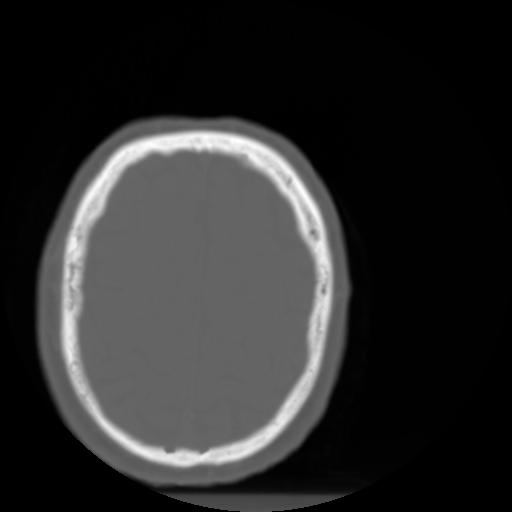

3 CEREBRO,,Axial,3.0,CEREBRO,,